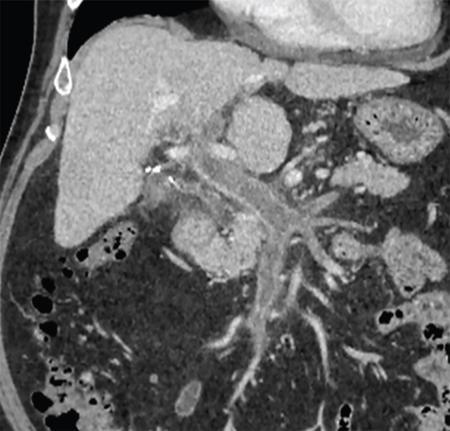

While evaluating PVT, it is essential to distinguish between bland (Fig. 9.14.2) and tumour thrombus as presence of portal vein tumour thrombus (PVTT) in major portal vein can contraindicate the liver transplant. Imaging characteristics of tumour thrombus include a contiguous thrombus with an adjacent mass showing characteristic imaging features of HCC or other malignancy, distension of the portal vein by endoluminal thrombus showing contrast enhancement on the postcontrast arterial phase (Fig. 9.14.3), and thrombosis in the setting of significantly elevated alpha-fetoprotein.

It is important to know presence and extent of portal vein thrombus before liver transplant because any unexpected thrombosis or narrowing of portal vein, can increase the operative time for vascular reconstruction, will need modifications in the surgical techniques like requirement for graft placements and also sometimes can result in graft ischemia due to prolongation of time taken for these. On the other hand, prior knowledge of PVT can help the surgeon to plan appropriate surgical strategies/procedures like intraoperative thrombectomy in case of acute or subacute thrombus or planning of venous ‘jump – grafts’ to SMV or splenic vein in case of chronic PVT (refer to Fig. 9.14.1).